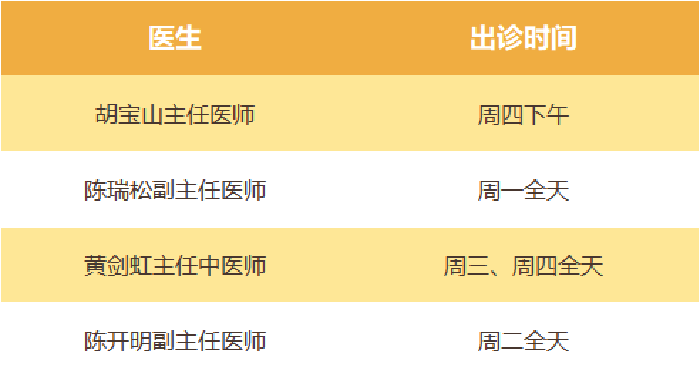

中医骨伤科进一步咨询 中医骨伤科出诊专家一览表